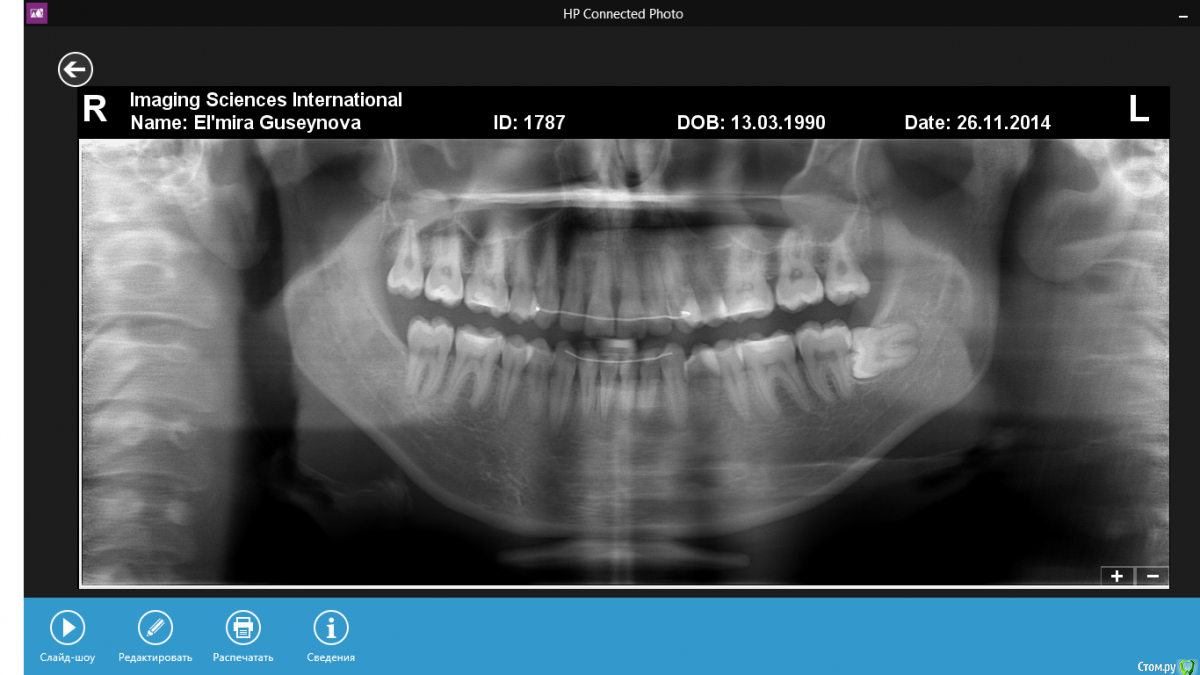

Эльмира242 Опубликовано 22 января, 2015 Автор Поделиться Опубликовано 22 января, 2015 Это ОПТГ после лечения) Ссылка на комментарий

Yana guapa Опубликовано 23 января, 2015 Поделиться Опубликовано 23 января, 2015 Жаль, что снимок обрезанный сверху - сустав не видно!(( а почему не удаляете восьмерку внизу? или уже удалили? Вам предложили несколько вариантов лечения, скажем, минимум и максимум, теперь Вам надо выбрать и найти, кто Вам это лечение осуществит! Ссылка на комментарий